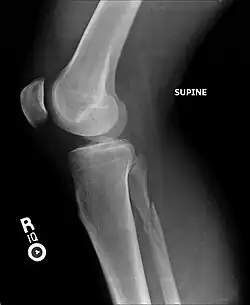

Ankle radiographs are used to detect widening of the tibiofibular syndesmosis or medial clear space. The medial clear space is the area between the talus of the ankle and the medial malleolus. Damage to the deltoid ligament and syndesmotic ligaments result in mortise instability, causing the talus to laterally shift and widen the medial clear space.[4][12] A clinical study, conducted in 2006 and published in the Journal of Bone and Joint Surgery, found that the medial clear space size of a normal ankle and an injured ankle measured at 4 millimetres and 5.4 millimetres in length respectively.[11] To confirm diagnosis, full-leg radiographs are used to inspect for fractures of the proximal fibula and widening of the interosseous clear space (or tibiofibular clear space). The interosseous clear space is the area between the medial side of the fibula and lateral side of the tibia. A peer-reviewed study, published in Injury in 2004, found that an interosseous clear space greater than 10 millimetres indicates diastasis of the syndesmotic ligaments.[4]

If necessary, computed tomography (CT) or magnetic resonance imaging (MRI) may also be used to clarify diagnosis. MRI scans can check for interosseous membrane or tibial tubercle damage if high instability of the ankle is diagnosed.[8][11] Arthroscopy may be used to diagnose a syndesmotic lesion but is often not recommended due to operative difficulty.[13] Stress radiographs of the ankle are used to assess the integrity of the deltoid ligament and tibiofibular syndesmosis.[9][13] The size of the medial clear space can also be measured using stress radiography.[11]

X-ray, CT, or MRI scans can be used to diagnose the extent of the Maisonneuve fracture's damage and determine whether it is a simple or comminution fracture.[8] During diagnosis, a supination-external rotation pattern of injury may also be concluded if there is an isolated fracture of the posterior tubercle of the tibia.[9]